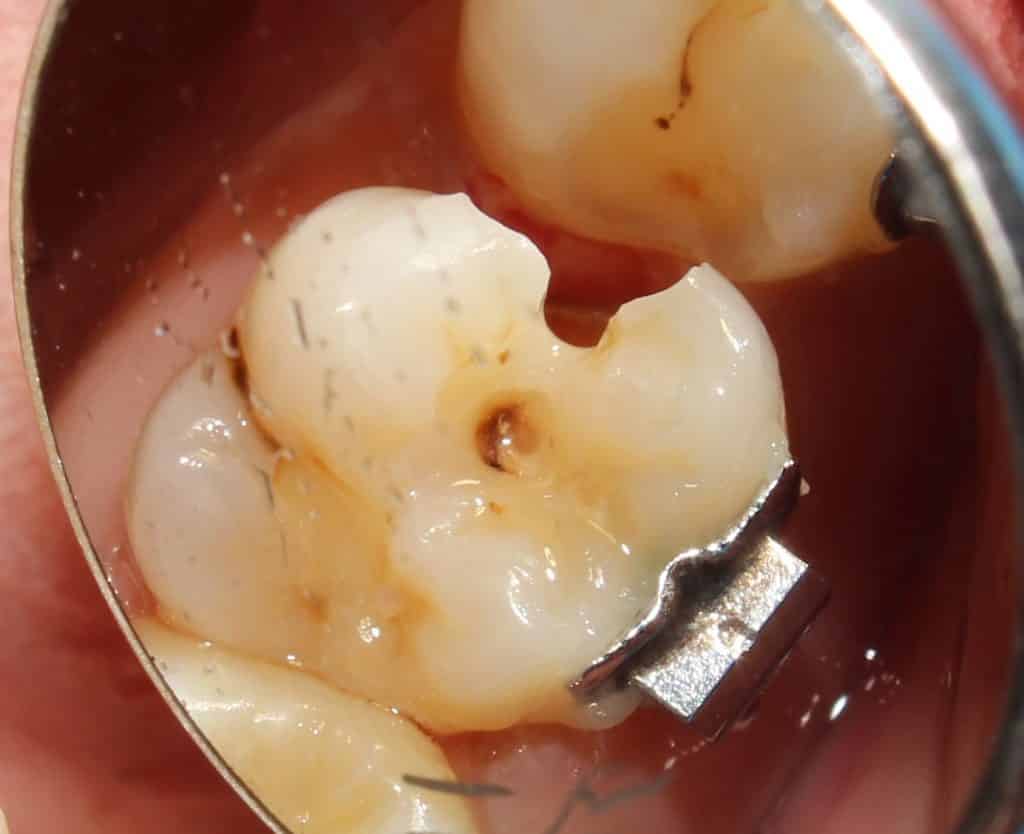

as caries removal is started.. the extent of the decay is noted..

caries removal on 14 is complete